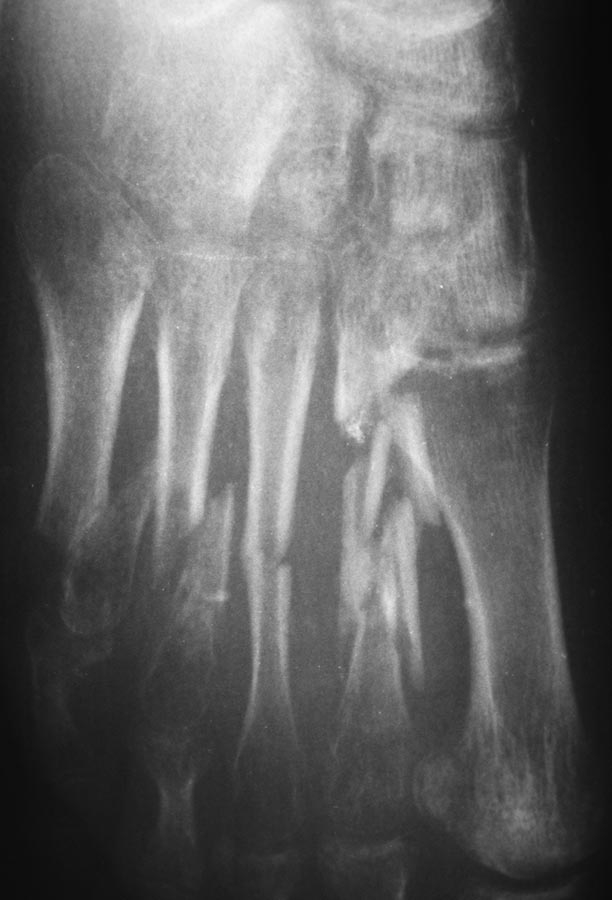

Пациентка 19 лет 11.05.13 получила травму в результате ДТП. диагноз: Открытые 3а степени оскольчатые переломы диафиза 2-5 плюсневых костей, перелом проксимальной фаланги 5 пальца, разрыв сухожилия разгибателя 4 пальца правой стопы.

При поступлении выполнено ПХО открытых переломов, фиксация спицами. Рана тыла стопы заживала без воспаления, однако имелся частичный некроз кожного лоскута. По снятии швов произведена иммобилизация циркулярной повязкой. Снимки стопы через 2,5 мес. иммобилизации.

Кроме переломов плюсневых костей, как мне кажется, есть подвывих в суставе Лисфранка (2-3 плюсне-клиновидный) суставы.

Проксимальная головка II плюсневой в вывихе (?), IV-V плюсневые выполнил бы МОС с резекцией костной мозоли. Можно ЧЛХ мини пластинами типа "Конмет". Одновременно шов разгибателя или его пластика поверхностным разгибателем с другого пальца. Случай не простой. Желаю удачи.

Мне кажется, что продолжение иммобилизации через такой срок смысла не имеет. Она и так уже привела к развитию резко выраженного остеопороза. Нужно снимать гипс, давать нагрузку на стопу до легко терпимых болезненных ощущений в обуви на жесткой подошве. Если пациентка сможет ходить с полной нагрузкой - пусть ходит. Нагрузка в подобной ситуации должна ускорить сращение и постепенно уменьшить выраженность регионарного остеопороза. И со временем, по мере сращения костей и восстановления опороспособности стопы нужно будет уже решать, нужна ли операция и если нужна, то какая (укорочение ли сохранивших длину 1 и 3 плюсневых, артродез поврежденных суставов среднего отдела стопы или еще что).

Для формирования продольного свода стопы достаточно сильное смещение отломков 5-й плюсневой кости - возможно именно на это стоит обратить внимание. Все остальное должно срастись без проблем